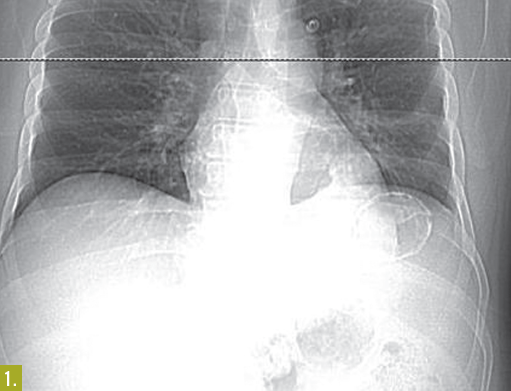

A 38-year-old man found lying on the floor in his home was hospitalized because of alcohol intoxication. A chest radiograph showed a large calcified lesion in the left upper abdomen (Figure 1). A CT scan with intravenous contrast revealed a large, well-defined, cystic mass with mural calcification in the spleen (Figure 2)

The CT findings were not consistent with a vascular malformation or echinococcal cyst—specifically, the mass was sharply demarcated, unilocular without septations, and round with a thin wall and attenuation similar to water. Urine Histoplasma antigen test results were negative.